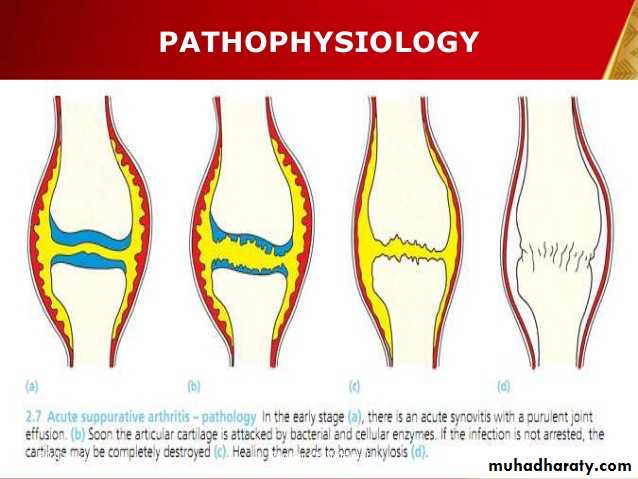

The infecting micro organisms settle in the synovial membrane inducing an acute inflammatory reaction. In the early stage (a), there is an acute synovitis with a seropurulent exudate and increase in synovial fluid.As pus appears in the joint, soon the articular cartilage is attacked by bacterial and cellular enzymes and eroded(b).

If the infection is not arrested, the cartilage may be completely destroyed (c). Healing then leads to bony ankylosis (d).